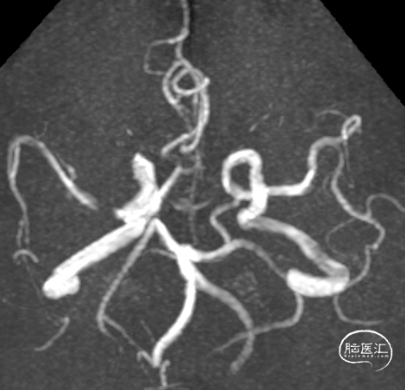

➢ 头颅MRA

左侧大脑前动脉A1段未见明确显示;左侧颈内动脉C4段、右侧颈内动脉C5段、右侧大脑中动脉M2段、左侧大脑后动脉P2段局部管腔狭窄。

头颅MRI+DWI+MRA:头颅MRI+DWI:1.DWI:右侧额顶叶、基底节区及侧脑室旁梗塞灶(急性期-亚急性期)。2.左侧额叶陈旧性病灶并周围胶质增生;双侧半卵圆中心缺血腔梗灶。3.左侧大脑前动脉A1段未见明确显示;左侧颈内动脉C4段、右侧颈内动脉C5段、右侧大脑中动脉M2段、左侧大脑后动脉P2段局部管腔狭窄。

造影显示左侧锁骨下动脉、右侧颈内动脉C5段、右侧大脑中动脉狭窄。左侧大脑前动脉A1段未见明确显示,左侧大脑后动脉局部管腔狭窄。